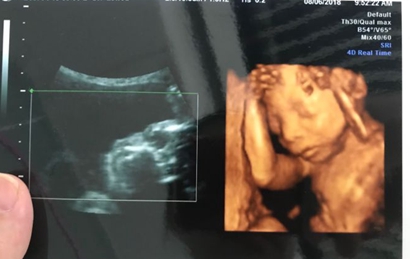

四维彩超最后结果出现问题也是有概率的,四维彩超虽然准确率十分高,但是在做检查的时候,难免会出现宝宝姿势不对,或者是胎儿的手部遮挡了生殖器的现象,导致医生的判断出错,当医生正在操作B超的时分,若宝宝正处于背部的姿态或手脚正好蜷到一同,从而遮挡了性别器官,这也会形成性别的改动,另外假如你家宝宝太调皮了,不太配合,姿态不对,医生也不可以很精确的看到Ta的生殖器,结果就没有那么精确了。

四维一般都是二十四周以后照的,这么大的孕周出错的机会还是比较小的,虽然不是百分之百准确的,但是出错的概率还是会比较少的,大部分情况都是不会出现翻盘的情况,四维超声同其它超声检查相比,可以实时观察人体内部器官的动态运动,也能准确地分辨出胎儿的性别。虽然四维彩超能够看清胎儿的性别,但在检查过程中,为了避免透露胎儿的性别,医生会主动的回避胎儿的性别特征以及下半身,因此最好找熟人的医生做这样才能更准确知道宝宝的性别。